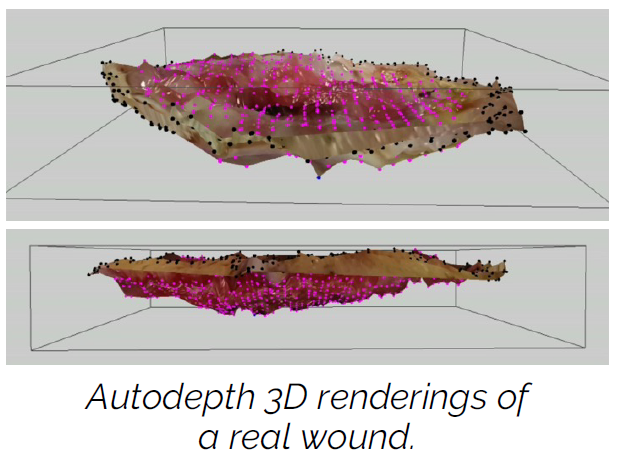

Validation of a Stickerless, Digital Automatic-Depth Measurement Feature within a Multi-Modal Wound Imaging Device

Dunham, D. et al. Presented at SAWC Fall 2024